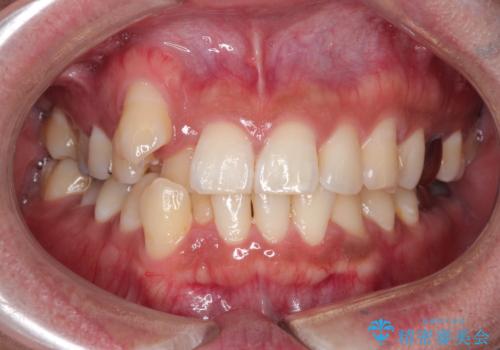

【ワイヤー矯正】八重歯と下の歯の凸凹を治したい

- 主訴:右上の八重歯と、下の歯の凸凹を治したい

上顎右側第一小臼歯と下顎右側第一小臼歯を抜歯しワイヤー矯正を行いました。

右側2級、左側1関係だったため、右側上下第一小臼歯を抜歯し、ワイヤー矯正を行いました。